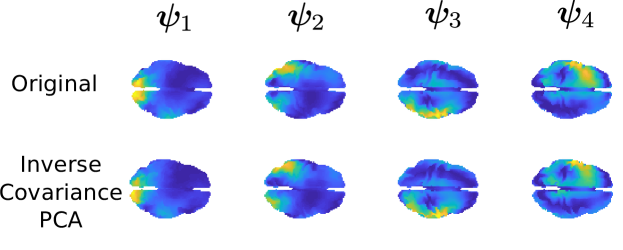

As in the previous section, we construct four orthonormal functions . The energy maps of are shown in Figure 9. We generate synthetic data from model (6) as follows:

where , …, are i.i.d realizations of the four independent random variables , with , , and . The matrix-valued form of the covariance functions arises from the fact that the observed functions on the brain space are vector-valued. Subsequently, we construct the point-wise evaluations matrices , from which the correspondent covariance matrices on the sensors space are defined as

The term is an error term, where is a matrix with each entry that is an independent sample from a Gaussian distribution with mean zero and standard deviation . We then apply Algorithm 2 with 15 iterations, feeding in input . The results are shown in Figure 9, in terms of energy maps of the reconstructed functions . These are a close approximation of the underlying functions . The fidelity measure of such estimates is , , and , for respectively, which is comparable in term of order of magnitude to the results obtained in the case of PCs of indirectly observed functions. Across the generation of multiple datasets, results are stable, with the exception of few situations where the cross-validation approach suggests a penalization coefficient that under-smoothes the solution, due to very similar associated signals on the sensors space of the under-smoothed solution and the real solution. However, the cross-validation is only a possible approach to the choice of the penalization constant, and many other options have been proposed in the inverse problems literature, (see, e.g., Vogel, 2002). Some of these, however, involve visual inspection.